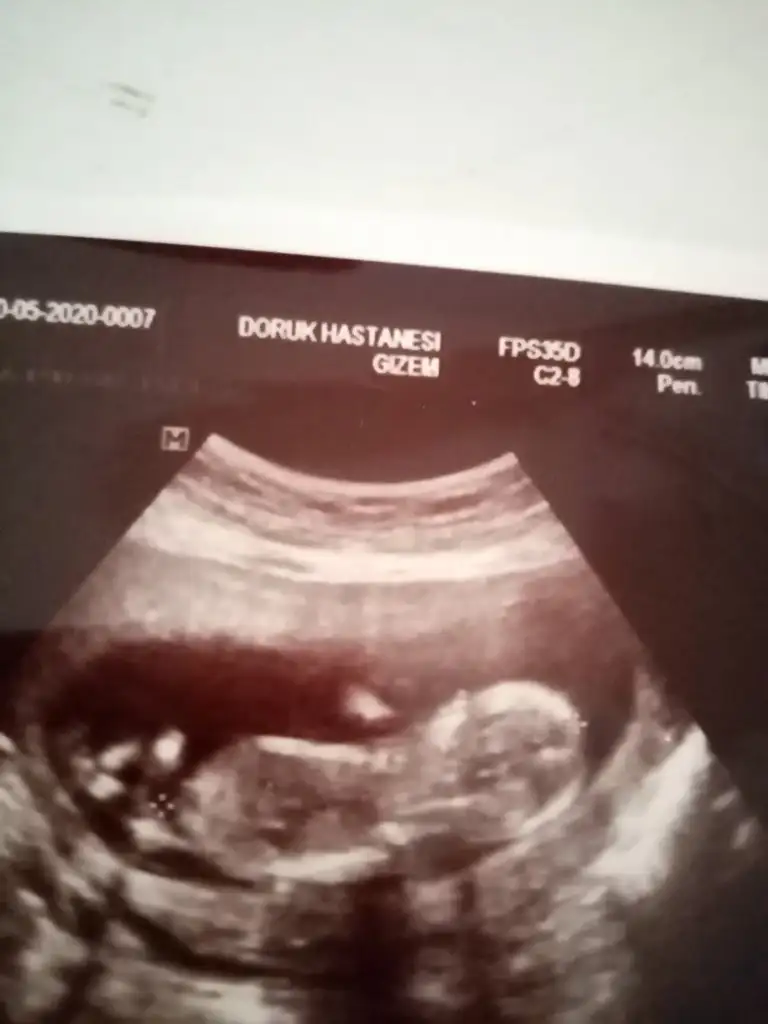

Net değil nubu karışık gibi ama eminde değilim erkek gibi usg 11 12 13 hafta olmalı tekrar usg paylaşınMerhaba tahminde bulunabilir misiniz Eki Görüntüle 2637373

Usgler puslu olursa 13 hafta tekrar paylaşın emin olamadım ilk bebekmi12. Hafta kontrolümden usg başka usgler de ekleyimEki Görüntüle 2637522

az sola yakın karından ise erkek buna göre nub için 11 12 13 haftalarıda paylaşın

Ayy hadi inşallah seninde erkektiraz sola yakın karından ise erkek buna göre nub için 11 12 13 haftalarıda paylaşın

Evet karından teşekkürleraz sola yakın karından ise erkek buna göre nub için 11 12 13 haftalarıda paylaşın